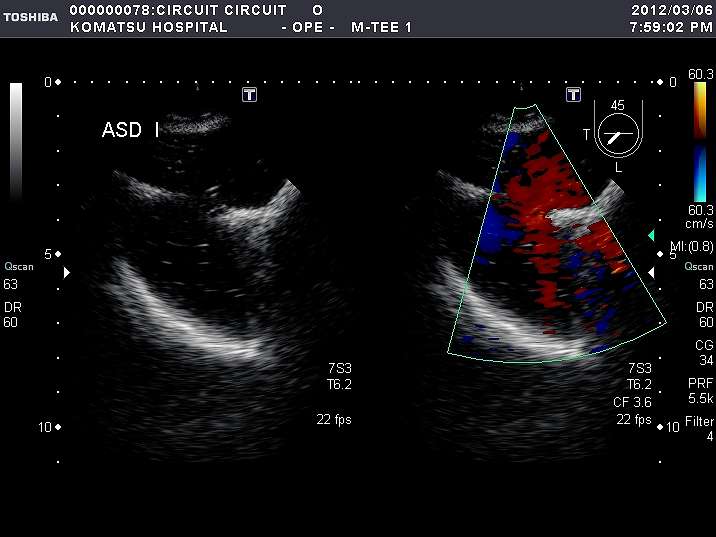

Circuit Lotusは、構造的心疾患(SHD)領域におけるASDトレーニングおよびデバイス評価のためのフローモデルとして開発されました。

解剖構造を“部分”ではなく“全体”として理解できること。